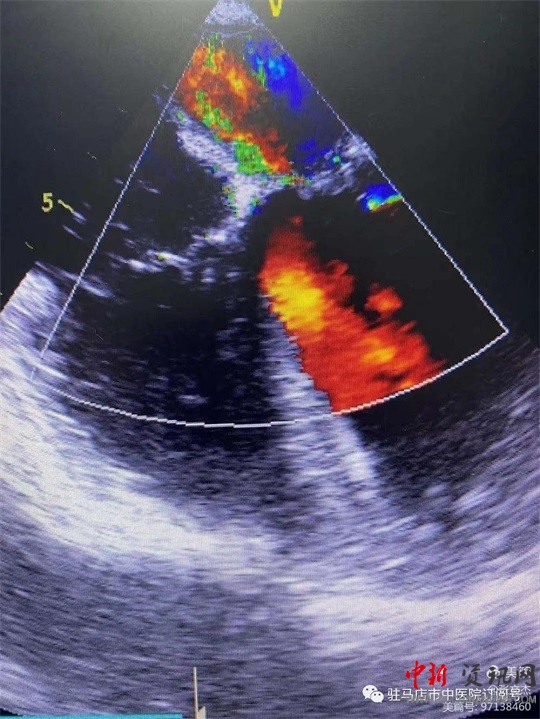

術(shù)前經(jīng)食道心臟超聲